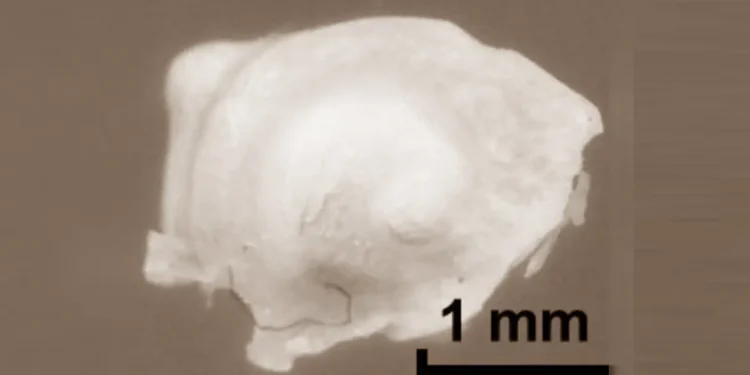

« L’utilisation de ce cristal a été déterminante », précise Kazunori Serita. « Elle a permis de créer une source de lumière térahertz compacte, capable d’interagir avec des échantillons de petite taille sans les endommager. » Les premiers tests ont été réalisés sur des cochlées de souris extraites et déshydratées. Les chercheurs ont comparé des échantillons vides à d’autres remplis d’un matériau réfléchissant les ondes térahertz, confirmant ainsi la capacité du système à pénétrer l’organe et à en distinguer les contours internes.

Légende illustration : Des chercheurs ont mis au point une nouvelle méthode d’imagerie térahertz qui a permis de visualiser les détails internes de la cochlée de la souris avec une résolution spatiale de l’ordre du micron. Une cochlée de souris excisée est illustrée. Crédit :Kazunori Serita, Waseda University